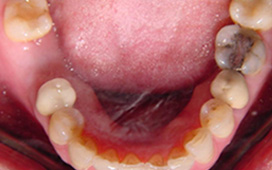

單顆雙植體 案例一